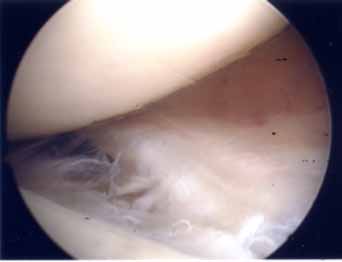

診断

階段昇降、膝屈伸動作や正座時の痛みが主体です。軽い例では日常生活では痛みがないものの運動時にのみ痛みが生じる例もあります。膝屈伸回旋テストでクリック音と疼痛の誘発で高率に診断できます。MRI検査は半月板損傷の診断にきわめて有効です。半月板の損傷形態は縦断裂、斜断裂が多く見られます。高齢者では変性(ばさばさ状)断裂が多くみられます。半月板の血行は周辺の10-25%までしか入っていないので、通常の半月板損傷は治癒しません